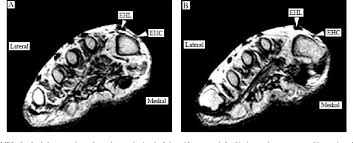

Coronal images are perpendicular to the long axis of the metatarsals. Accessory muscles are isointense to skeletal muscle on all pulse sequences, and can insert by fleshy muscular or tendinous insertions. Adductor hallucis is anatomically located in the central compartment of foot, but the muscle is functionally grouped with the medial plantar muscles of foot because it acts on the great toe (hallux). The adductor hallucis has two heads: Mri is an ideal method for identifying areas of muscle atrophy and fatty infiltration. The muscles lie within a flat fascia on the dorsum of the foot (fascia dorsalis pedis) and are innervated by the deep fibular or peroneal nerve. They are named extensor digitorum brevis and extensor hallucis brevis. The aim of this review is to provide the reader with a comprehensive overview of the magnetic resonance imaging (mri) characteristics of the most common benign and malignant soft tissue neoplasms which occur around the foot and ankle.

Extensor hoods and bases of proximal phalanges of toes iii to v action: As the fiber bundles extend distally, they become grouped into four bellies. Your doctor, with the help of a radiologist, can then examine these images to determine whether there is anything wrong with your foot or. They are named extensor digitorum brevis and extensor hallucis brevis. Routine ankle magnetic resonance imaging (mri) tests involve taking images of the foot and ankle in the axial, coronal, and sagittal planes parallel to the tabletop(2). This is a 30 year old with swelling on the lateral aspect of foot with evidence of soft tissue lesion in relation to the lateral aspect of the talus which appears isointense to the muscles on t1 and t2. Anatomy of the foot and ankle mri / magnetic resonance imaging, otherwise known as mri, uses a combination of magnetic fields and radio waves to take images of the internal structures of your body. In the foot and ankle many accessory ossicles can be seen.

The muscles lie within a flat fascia on the dorsum of the foot (fascia dorsalis pedis) and are innervated by the deep fibular or peroneal nerve.